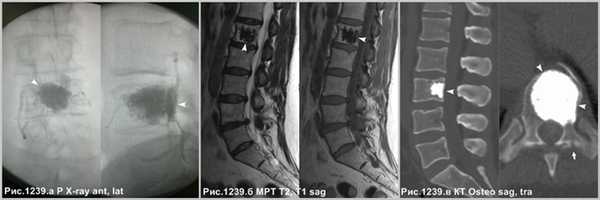

![heangioma_9]()

Итраоперационный рентгеновский контроль, посредством электронного оптического преобразователя, демонстрирует компактный участок плотного медицинского цемента, выполняющего полость крупной гемангиомы (головки стрелок на рис.1239.а), после вертебропластики, призванный стабилизировать тело пораженного позвонка и предотвратить вероятность патологического перелома. Следы вертебропластики в виде участка остеосклероза на МРТ (головки стрелок на рис.1239.б) и на КТ (головки стрелок на рис.1239.в). Визуализируется канал от прохождения иглы в левой дужке позвонка (стрелка на рис.1239.в).